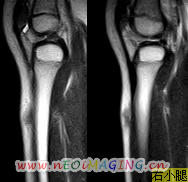

标题: PED0931:男,5岁,发现双小腿软组织肿块1年,质地中等,无 [打印本页]

标题: PED0931:男,5岁,发现双小腿软组织肿块1年,质地中等,无